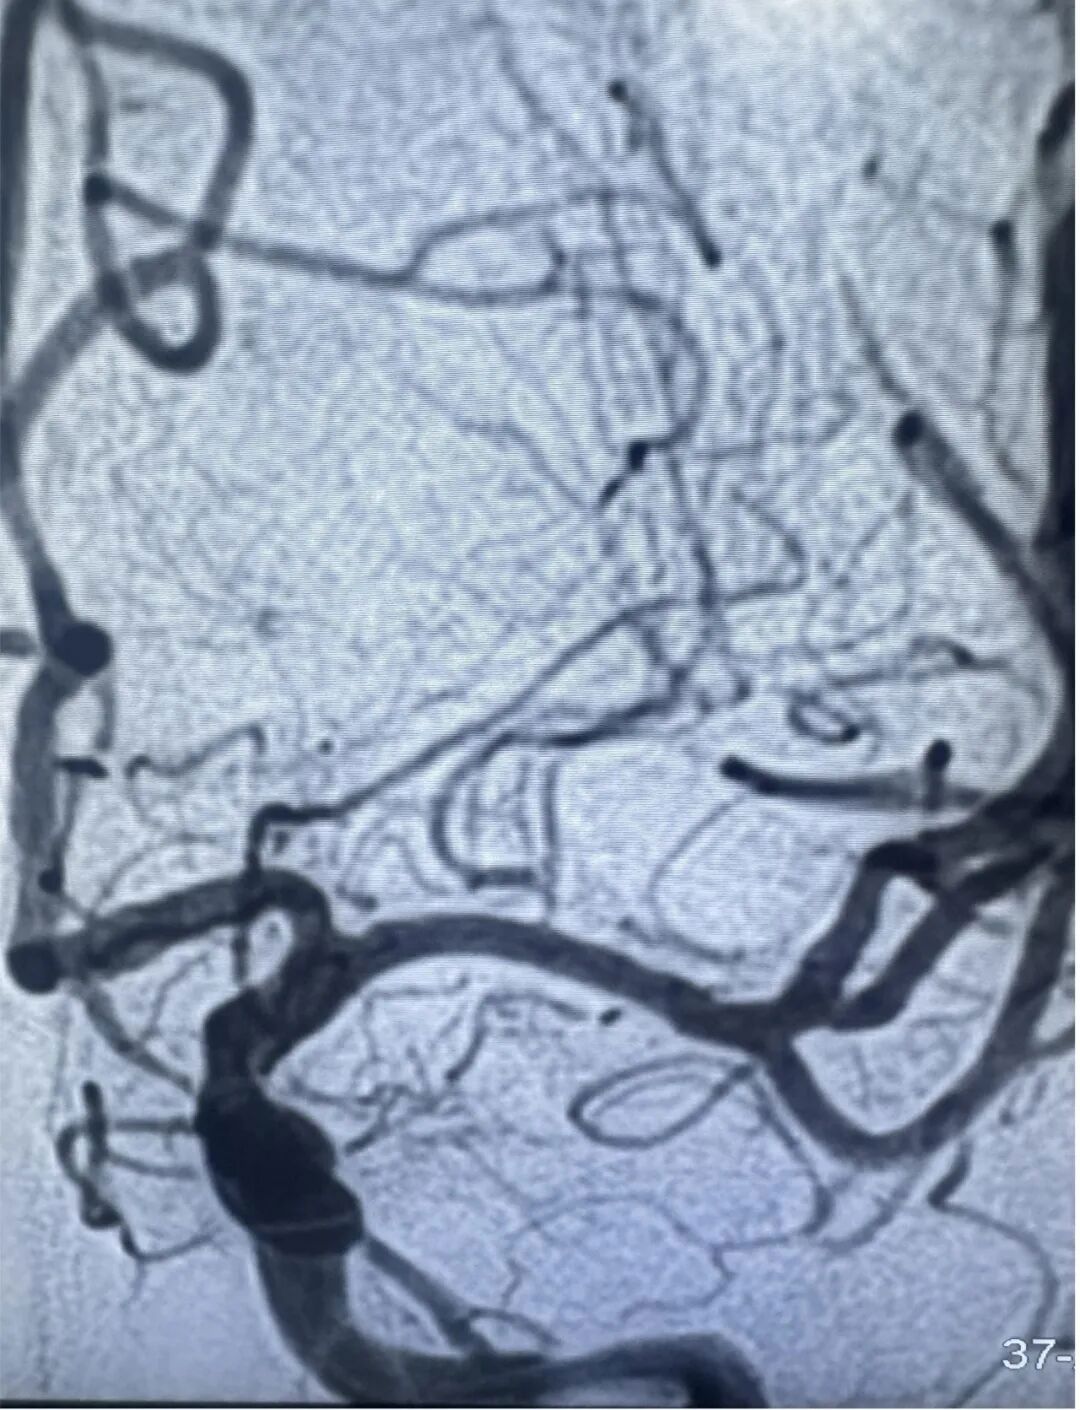

大脑中动脉的直径平均为2.7mm,更细者可达到1.5mm,血管狭窄不完全可怕,可怕的是远端血流受限缺血,其上发出的一丛丛小血管常常是导致脑梗塞或脑出血的元凶。吴先生大脑中动脉重度狭窄但还没有完全闭塞,提醒了他两次,就是为了让他能意识到并消除掉这些危险因素。

颅内血管纤细且脆弱,正常血管也只有2.25毫米,在重度狭窄的颅内血管内放置支架是一项严峻挑战。郭宗培、陈历、熊建医生、聂毅医生团队,身披重达15斤的铅衣,操控堪比头发丝样的导丝,球囊适度扩张狭窄血管,精准释放颅内药物涂层支架,使血管狭窄解除,远端血管再次丰富充盈,为减少以后发生脑梗塞的可能性打下坚实基础。整个过程需要团队的团结紧密协作,这场手术考验的是医生的整体医疗素质。